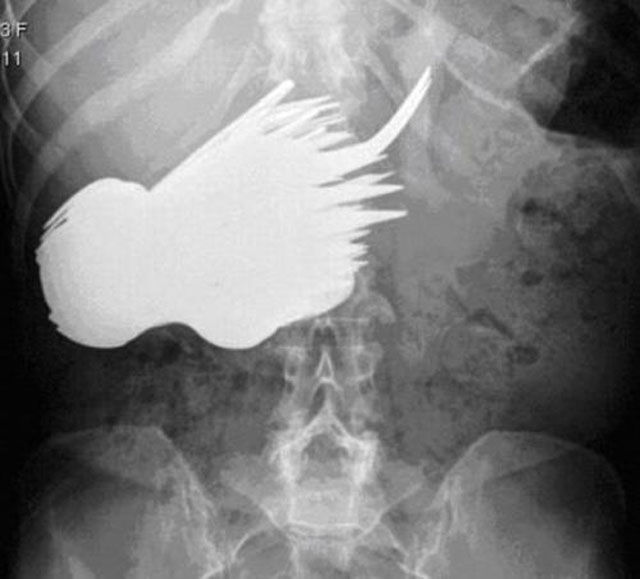

52-year-old Dutchwoman Margaret Daalman came to hospital complaining of stomach ache, and one glance at her X-ray shows why.Surgeons in Rotterdam in the Netherlands were astonished when X-rays showed 78 different items of cutlery in her stomach.